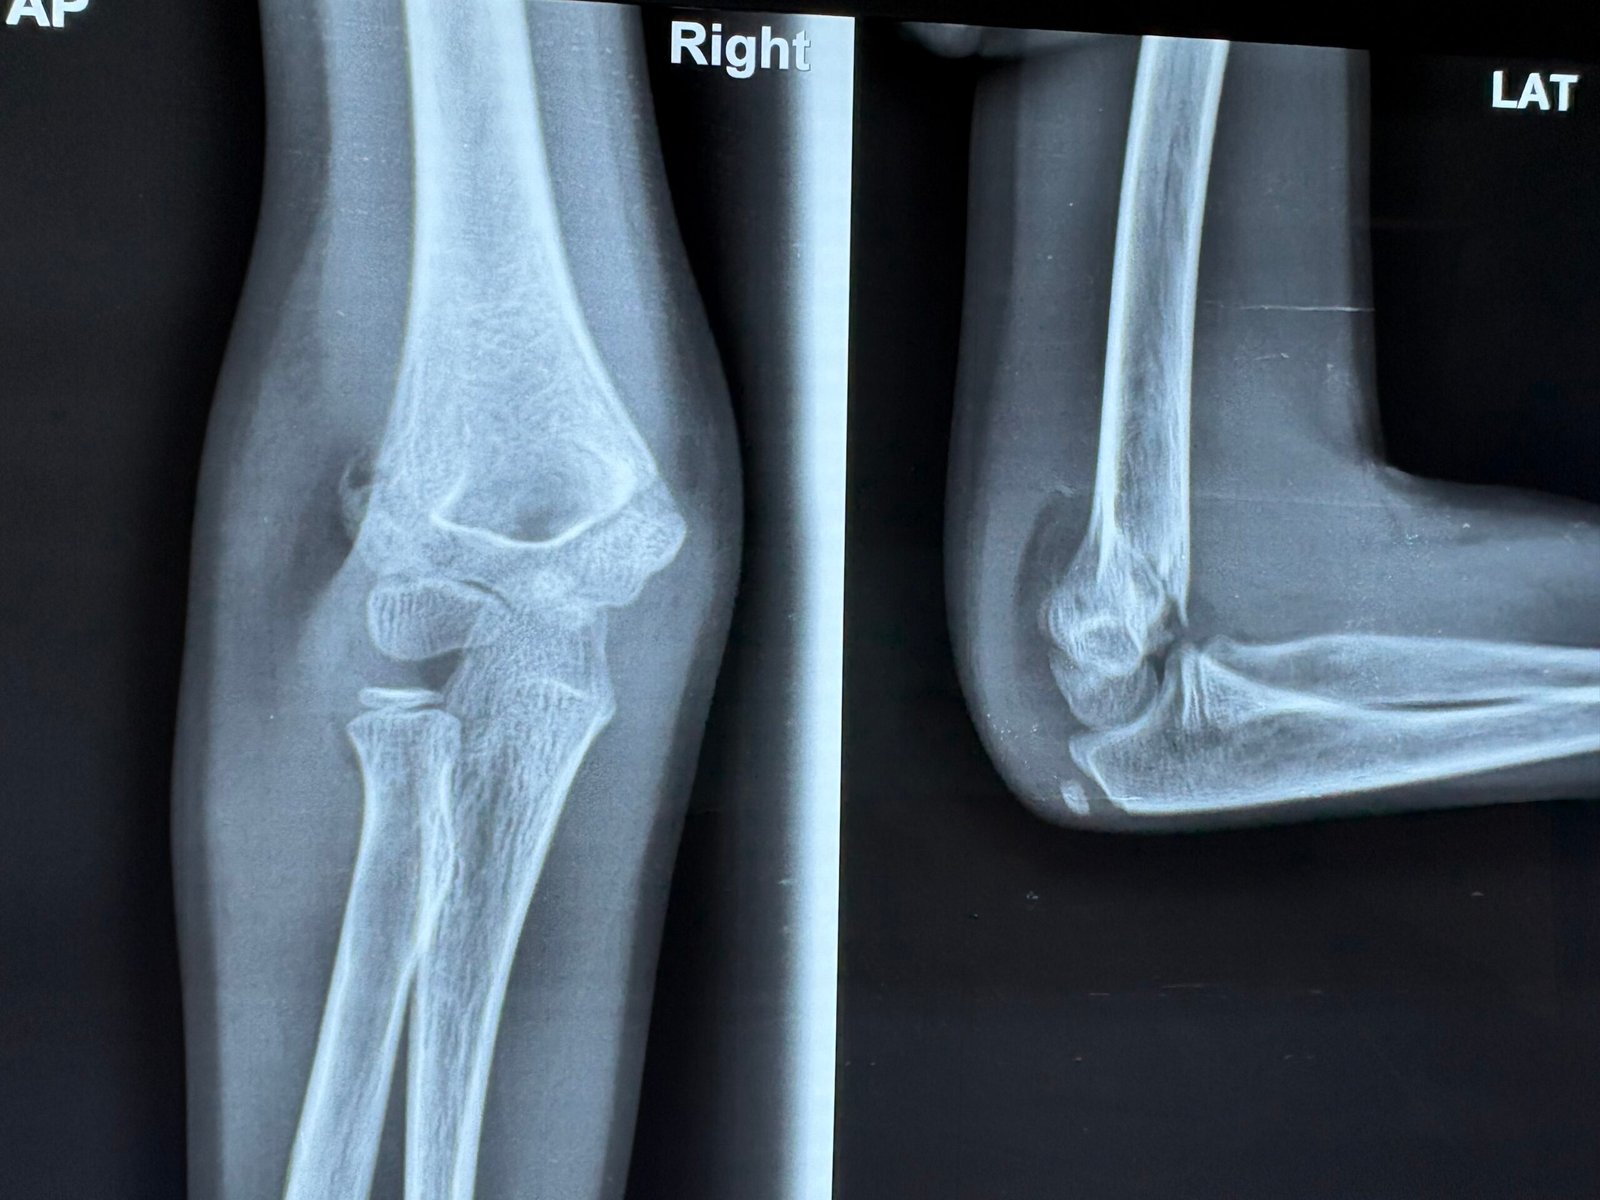

Shoulder & Upper Limb Care

Expert solutions for frozen shoulder, rotator cuff tears, and dislocations. We utilize a combination of targeted exercises, pain management, and specialized surgery to restore full range of motion.